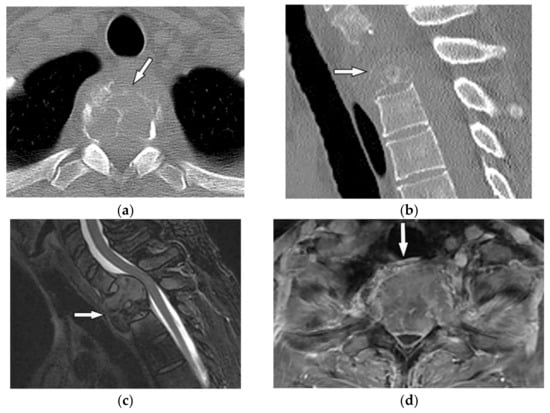

Cortical expansion with lobulated border, abundant peripheral sclerosis, and rarely internal calcification are the main radiologic appearances of chondromyxoid fibroma on radiograph and CT [3,33]. Cortical expansion with lobulated border, abundant peripheral sclerosis, and rarely internal calcification are the main radiologic appearances of chondromyxoid fibroma on radiograph and CT [3,33]. On MRI, varying degrees of signal intensity can be identified. Isointensity on T1-weighted and intermediate to high intensity on T2-weighted images have been reported. Peripheral hypointense rim seen on both T1-weighted and T2-weighted images reflects the sclerotic rim. The absence of diffusion restriction and diffuse moderate to intense contrast enhancement is noticeable (Figure 10) [3,33]. The absence of diffusion restriction and diffuse moderate to intense contrast enhancement is noticeable (Figure 10) [3,33].

Figure 10.

A 26-year-old man with right chest pain. The axial contrast-enhanced CT in soft tissue (a) and bone window (b) demonstrate well-defined oval eccentric lytic bone lesion within the posteromedial aspect of the chest wall on the right side (arrow) without intracanal extension or periosteal reaction; adjacent focal vertebral body scalloping is also shown. (c,d) Axial T1W and T2W show low signal intensity in T1W and intermediate to high intensity in T2W with the peripheral hypointense rim due to the sclerotic rim (arrow).